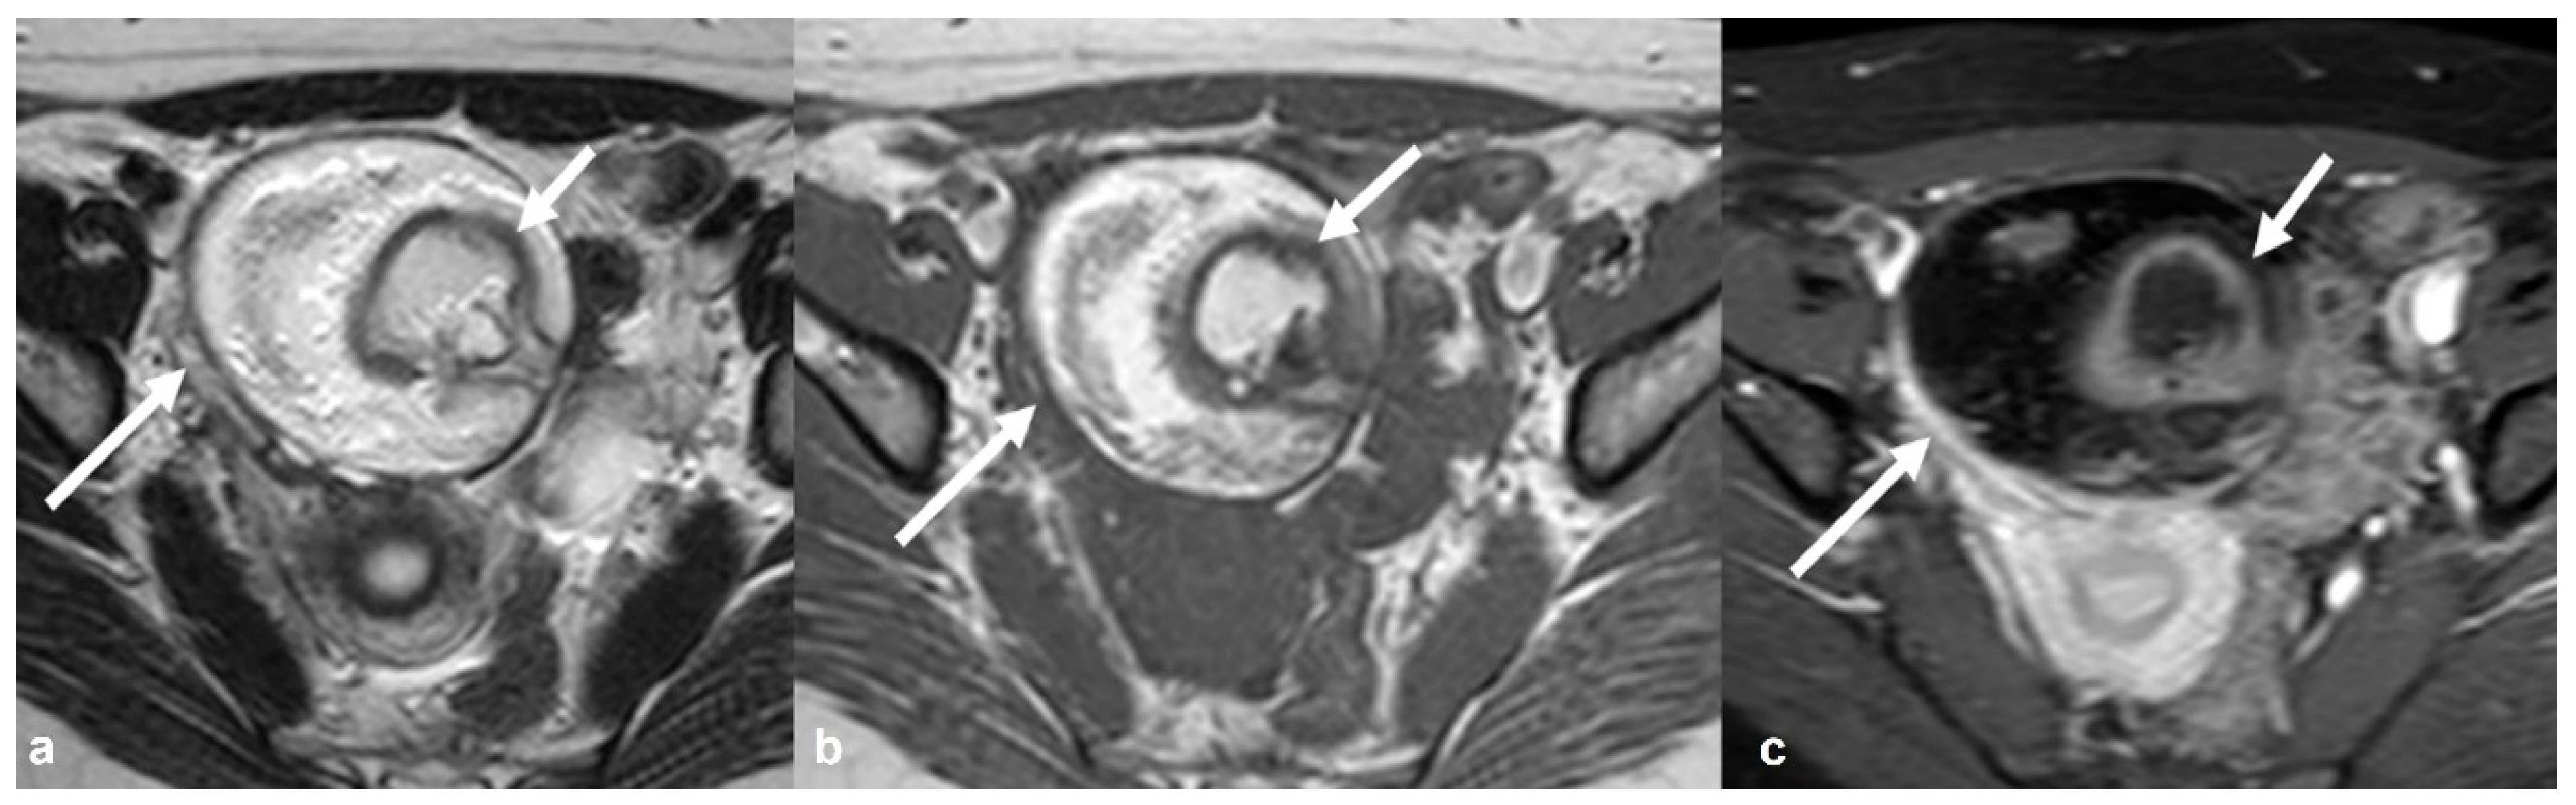

2.4.1. Mature Cystic Teratoma (Dermoid)

2.4.2. Immature Teratoma

2.4.3. Dysgerminoma